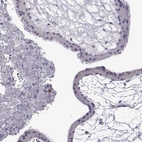

Immunohistochemistry analysis in human cerebral cortex and prostate tissues using HPA072505 antibody. Corresponding VGF RNA-seq data are presented for the same tissues.